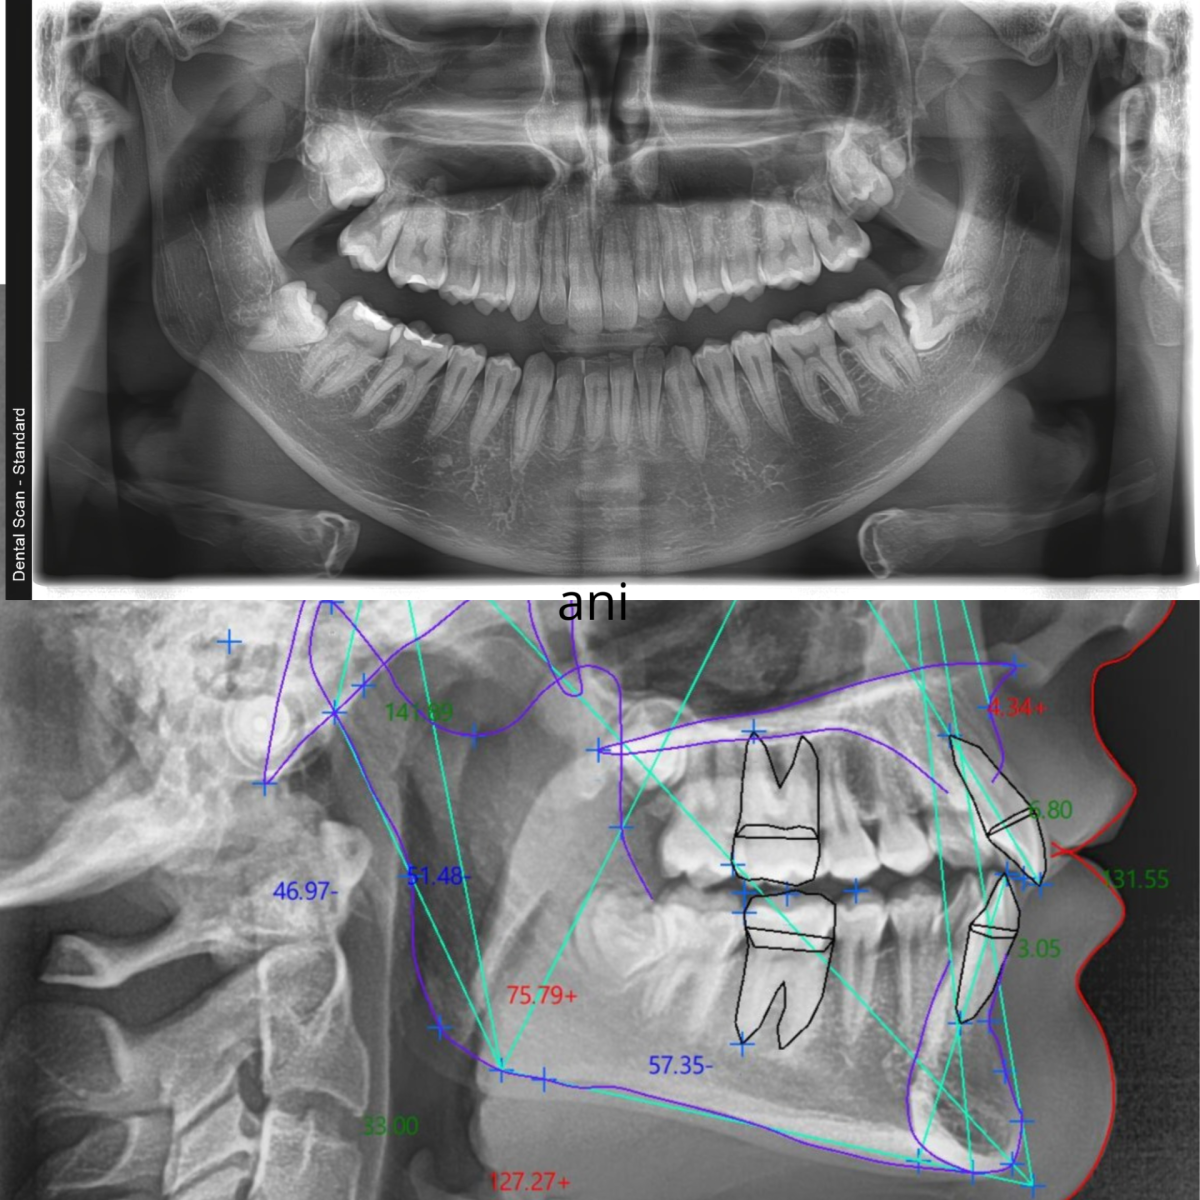

Dva snimka za početak ortodontskog lečenja

Kada ortodont kaže „treba nam snimanje pre postavke“ — najčešće misli na dva snimka: ortopan i telerendgen (kefalogram). Ova kombinacija nije slučajna. Svaki od ova dva snimka daje drugačiju vrstu informacija, a zajedno čine potpunu dijagnostičku osnovu bez koje se ortodontsko lečenje ne planira — ni za decu, ni za odrasle.

Telerendgen, stručno nazvan lateralni cefalogram (eng. Lateral Cephalometric Radiograph), standardizovan je rendgenski snimak glave u profilu. Za razliku od ortopana koji prikazuje zube, telerendgen prikazuje odnos kostiju lica i vilica — i to na način koji omogućava precizno merenje.

Snimanje se radi sa tačno definisane udaljenosti od 1,5 metra, a glava pacijenta se pozicionira u specijalnom nosaču (cefalostatu): dva fiksatora u spoljašnjim ušnim hodnicima, zubi u centralnoj okluziji, a Frankfurtska ravan horizontalno. Ova standardizacija je ključna — jedino tako se rezultati mogu porediti u vremenu i planirati lečenje sa preciznošću.

Šta se vidi na telerendgenu?

Na kefalogramu se jasno uočavaju sve važne koštane tačke lica, na osnovu kojih se crtaju uglovi i ravni. Najvažniji elementi analize su:

Anatomske tačke:

- Sela (S) — centralna referentna tačka baze lobanje

- Nasion (N) — tačka između čela i nosa

- Tačka A — najdublja tačka prednje ivice gornje vilice (maksile)

- Tačka B — najdublja tačka prednje ivice donje vilice (mandibule)

- Gonion (Go) — ugao mandibule

- Menton (Me) i Pogonion (Pog) — tačke brade

Ključni uglovi i šta znače:

| Merenje | Prosek (Eastman standard) | Šta pokazuje |

|---|---|---|

| SNA ugao | 81° ± 3° | Položaj gornje vilice prema bazi lobanje |

| SNB ugao | 78° ± 3° | Položaj donje vilice prema bazi lobanje |

| ANB ugao | 3° ± 2° | Odnos gornje i donje vilice (skeletna klasa) |

| Ugao gornjeg sekutića | 109° ± 6° | Nagib prednjih zuba gornje vilice |

| Ugao donjeg sekutića | 93° ± 6° | Nagib prednjih zuba donje vilice |

| Interincizalni ugao | 135° ± 10° | Odnos između prednjih zuba — dubina zagrižaja |

| MMPA ugao | 27° ± 4° | Vertikalni obrazac rasta vilice |

ANB ugao je posebno važan za ortodonta: vrednost 2–4° znači normalan (Klasa I) odnos vilica, ispod 2° ukazuje na prognatizam donje vilice (Klasa III), a iznad 4° na retruziju donje vilice ili protruziju gornje (Klasa II). Na osnovu ove vrednosti ortodont zna sa čime radi — i bira terapiju koja odgovara uzroku, ne samo simptomu.